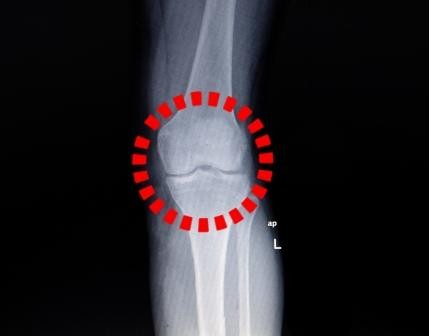

Bij een trauma van de knie is het verleidelijk om de anamnese af te raffelen en over te gaan naar het lichamelijk onderzoek. Maar hoe betrouwbaar zijn anamnese en onderzoek om bijvoorbeeld een voorste kruisbandruptuur (VKB) vast te stellen? En kan de huisarts dat net zo goed als de orthopeed?

In een Rotterdams onderzoek werden 60 patiënten onderzocht door een ervaren huisarts en orthopeed. Na een standaardanamnese voerden beide artsen een lichamelijk onderzoek uit, met daarin de Lachman-test, de Pivot shift-test, en de voorste schuifladetest. Ze schatten of er een VKB-ruptuur was op basis van alleen de anamnese en daarna op basis van anamnese en lichamelijk onderzoek. De gouden standaard was arthroscopie, waarbij 22 patiënten een VKB-ruptuur bleken te hebben.

Op basis van alleen anamnese was er weinig verschil: de orthopeed zat er in 15 van de 60 patiënten naast (8 vals-positief en 7 vals-negatief), en de huisarts in 17 van de 60 patiënten (4 vals-positief en 13 vals-negatief). Dit kwam neer op een positief en negatief voorspellende waarde (PVW en NVW) van respectievelijk 65 en 81% voor de orthopeed en 69 en 72% voor de huisarts. Vier anamnese-items waren extra voorspellend voor een VKB-ruptuur: het gehoord hebben van een krak of knap, zwelling direct na het trauma, het gevoel ‘door te knie te zakke’, en een onstabiel gevoel. Wanneer de orthopeed anamnese en lichamelijk onderzoek combineerde, ging hij beter voorspellen (PVW 94%; NVW 86%), maar de huisarts niet (PVW 62%; NVW 77%).